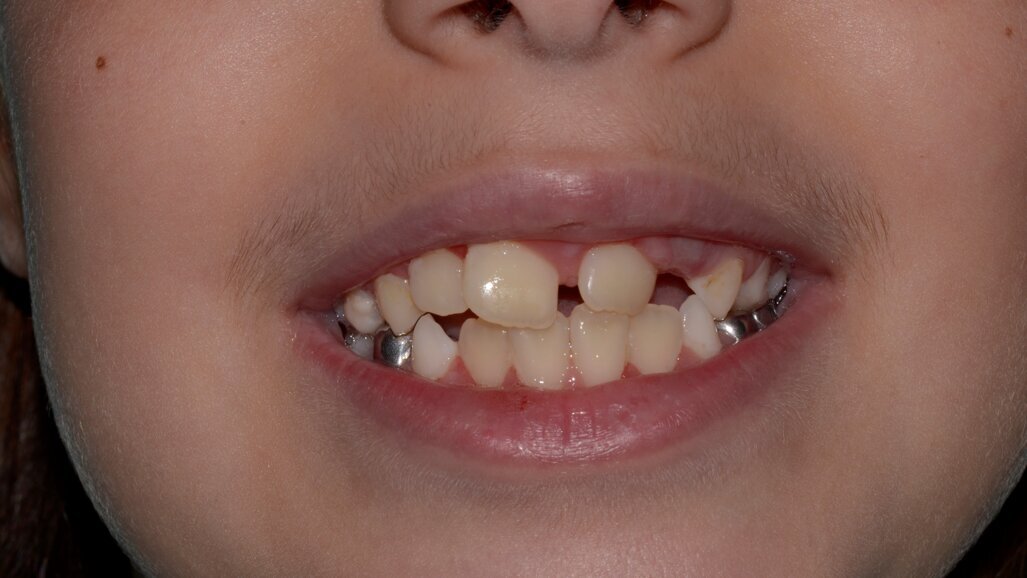

An eight and half year-old girl (LT) attended the paediatric dentistry department of Hamdan Bin Mohammed College of Dental Medicine (HBMCDM) in Dubai Healthcare City for an opinion. The patient’s mother was concerned about the delayed eruption of an upper front tooth (21) that was affecting her child’s appearance (Figs. 1 a, b & c). LT was medically fit and healthy with no history of previous dental trauma. She was in the mixed dentition stage. Tooth 11 had erupted 4 months ago in cross bite but 21 had not erupted yet. Its eruption was much delayed (usually erupts at 7 ½ years of age). Looking back at previous x-rays, a DPT was taken a year ago and it was noticed that an important feature was missed. Retrospectively, the presence of a supernumerary tooth ($) in the area of 21 and congenital missing 47 was confirmed (Fig. 2). Two new x-rays, namely upper intra oral periapicals and the parallax technique (distal shift) showed a supernumerary tooth (conical and inverted) in a palatal position (Figs. 3 a & b). LT also had dental caries of her primary teeth (Figs. 4 a & b), had a pronounced gag reflex and was dentally anxious.

Figs. 1 (a, b & c). An 8 ½ year old girl presented with delayed eruption of 21 and a palpable palatal swelling. Lower teeth were carious; see bitewings in Figure 4